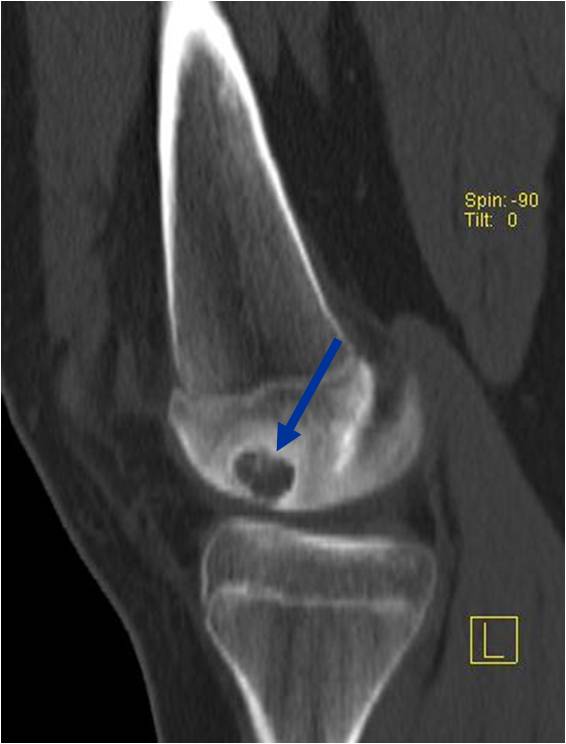

Radiographic Presentation

- Presents as a highly defined/well circumscribed geographic oval/round lytic defect

- Surrounded by rim of sclerotic bone

- Usually in epiphyseal region

- Lesion ranges from 3 cm to 6 cm diameter

- Usually radiolucent

- May have fine trabeculae and irregular calcifications

- Calcifications are often better detected with a CT scan but are not uniformly present

- Lesions may expand the bone and new periosteal bone may form

- Bony end plate, cortex, bone contour are unaffected

- (Plain x-ray appearance)

- Geographic lytic lesion IA/IB margin of sclerosis

- Usually Eccentric more often than Central in the bone

- Rarely expansile (rarely penetrates the cortex)

- Calcified chondroid matrix 30%-50% of cases

- Often better detected with a CT Scan

- Periosteal Reaction 30-50% of cases

- Usually occurs in Adjacent Diaphysis/Metaphysis since epiphysis is intraarticular and not surrounded by periosteum

- (CT appearance)

- Most useful for detecting subtle mineralization not apparent on X-rays

- Useful for identifying intact periosteum around any expansile soft tissue component

- surrounding thin reactive shell of bone/mineralization (Egg Shell Rim of Calcification)

- helps place the tumor in a benign category

- helps evaluate:

- bony quality

- extent of bone and cortical destruction

- whether the subchondral plate of bone adjacent to the articular cartilage has been destroyed or is intact